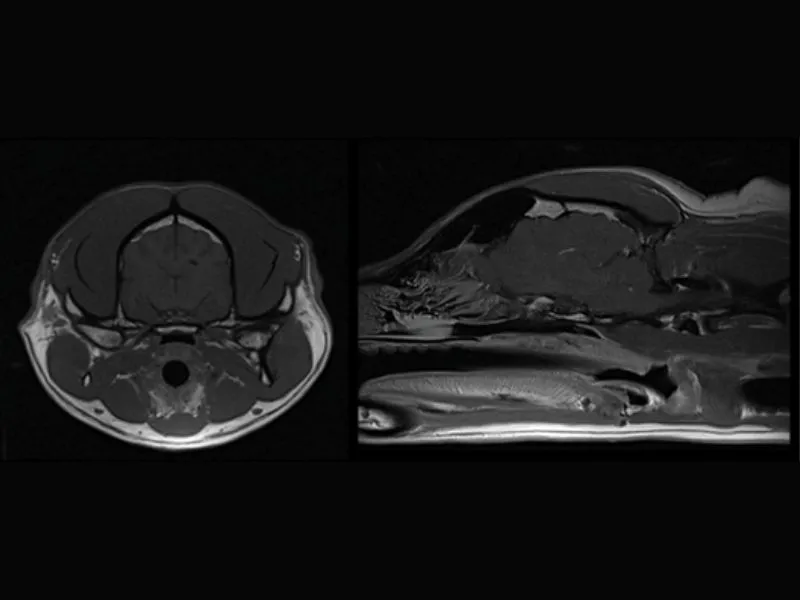

Supreme vet-mr – Transverse and sagittal T1W images of a normal canine brain